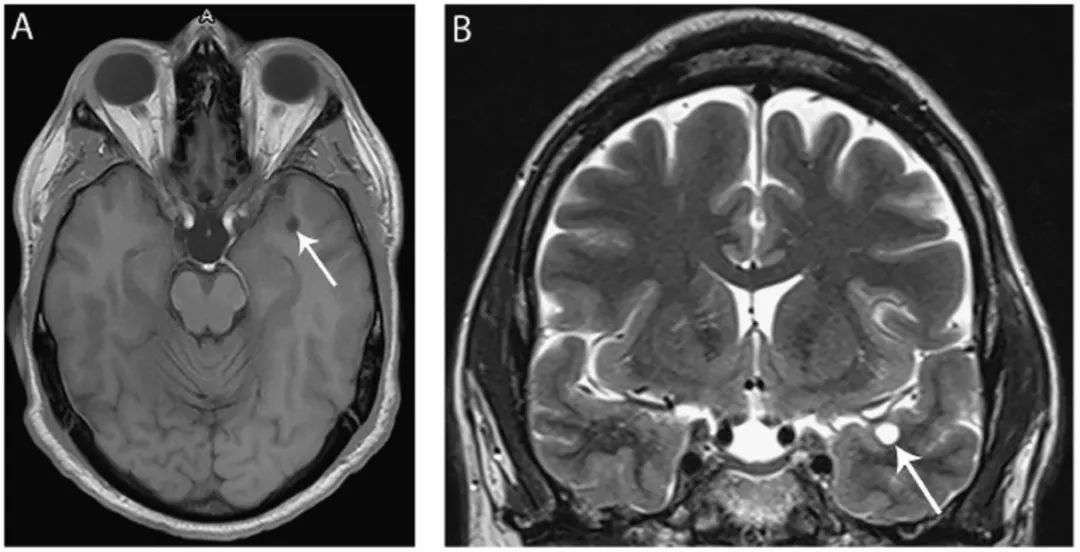

图4 小神经胶质囊肿

(A) 轴位T1WI像和冠状位T2WI像(B)显示左侧颞叶前方边界清晰的实质内囊肿(箭头),等CSF信号。